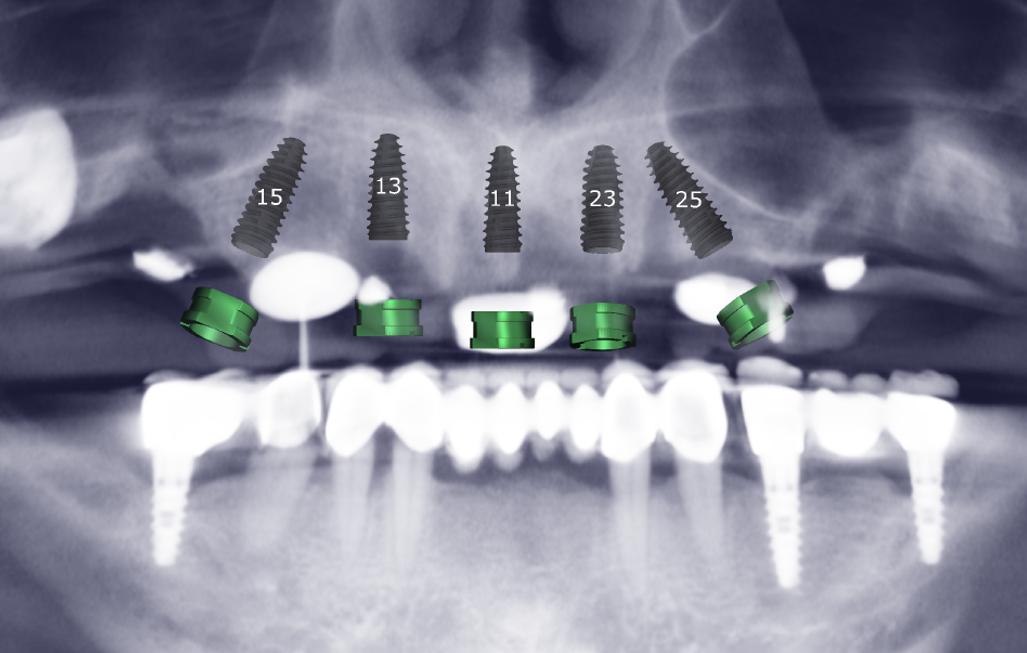

3D Planlama Önizlemesi

Alınan kayıtlarla oluşturulan sanal hastada ameliyat öncesi analiz imkanı

Sanaldan cerrahiye sapma minimizasyonu

Sinir, sinüs, kök mesafelerinin 3B değerlendirilmesi ve komplikasyon riskinin azaltılması

Protez Odaklı Planlama

• Protez odaklı planlama